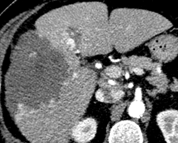

Lésions épithéliales hépatiques